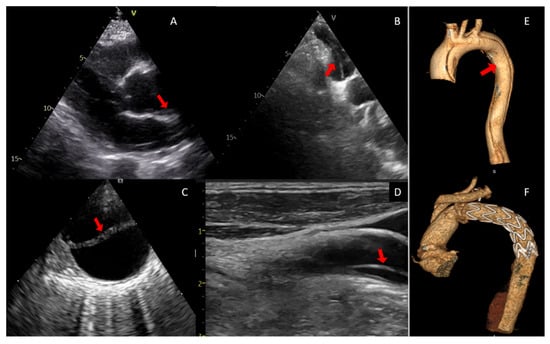

UC Irvine